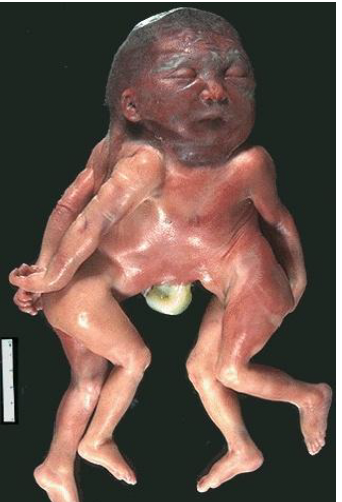

acardius-acephalus

incomplete fetus with legs and possible caudal organs

cranially amorphous mass of tissue with no heart or brain

complete acardiac twin

fetus with recognizable body regions and some poorly developed, non-functioning organs

blood pumped from one twin to another by retrograde flow